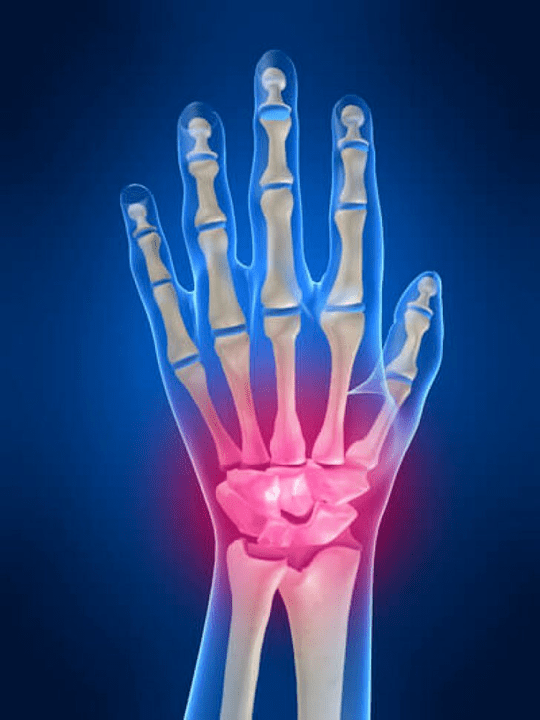

Zápästie

Zápästie je tvorený kosťami proximálnych kostí (horný) množstvo zápästia (Trihedral, polo -moon, Scaphoid Bones) a distálne oblasti žiarenia a lakťových kostí. Kosť lakťa nie je priamo spojená s kosťami zápästia, ale s pomocou distálneho (Znížiť) kĺbový disk. Táto štruktúra oddeľuje dutinu zápästia od distálnej dutiny (Znížiť) Dlaždice.

Kĺb zápästia

Spojy zápästia sú reprezentované tromi typmi kĺbov. Prvá forma obsahuje tie kĺby, ktoré sa nachádzajú medzi kosťami hornej časti (skafoidný, semi -moon, trihedrálny, hrachový) alebo dolný riadok (v tvare háčika, hlavičky, lichobežník, zachytávanie kostí). Tieto kĺby sa nazývajú medzichangeské kĺby. Podľa druhého typu je So -Called Mid -Wrist Coĺb zaradený. Tento kĺb má tvar v tvare S a je tvorený kvôli spojeniu kostí hornej a dolnej rady zápästia. Tretí typ obsahuje spoj kosti hrachu. Prostredníctvom tohto kĺbu je trihedrálna kosť spojená s hrachovou kosťou.